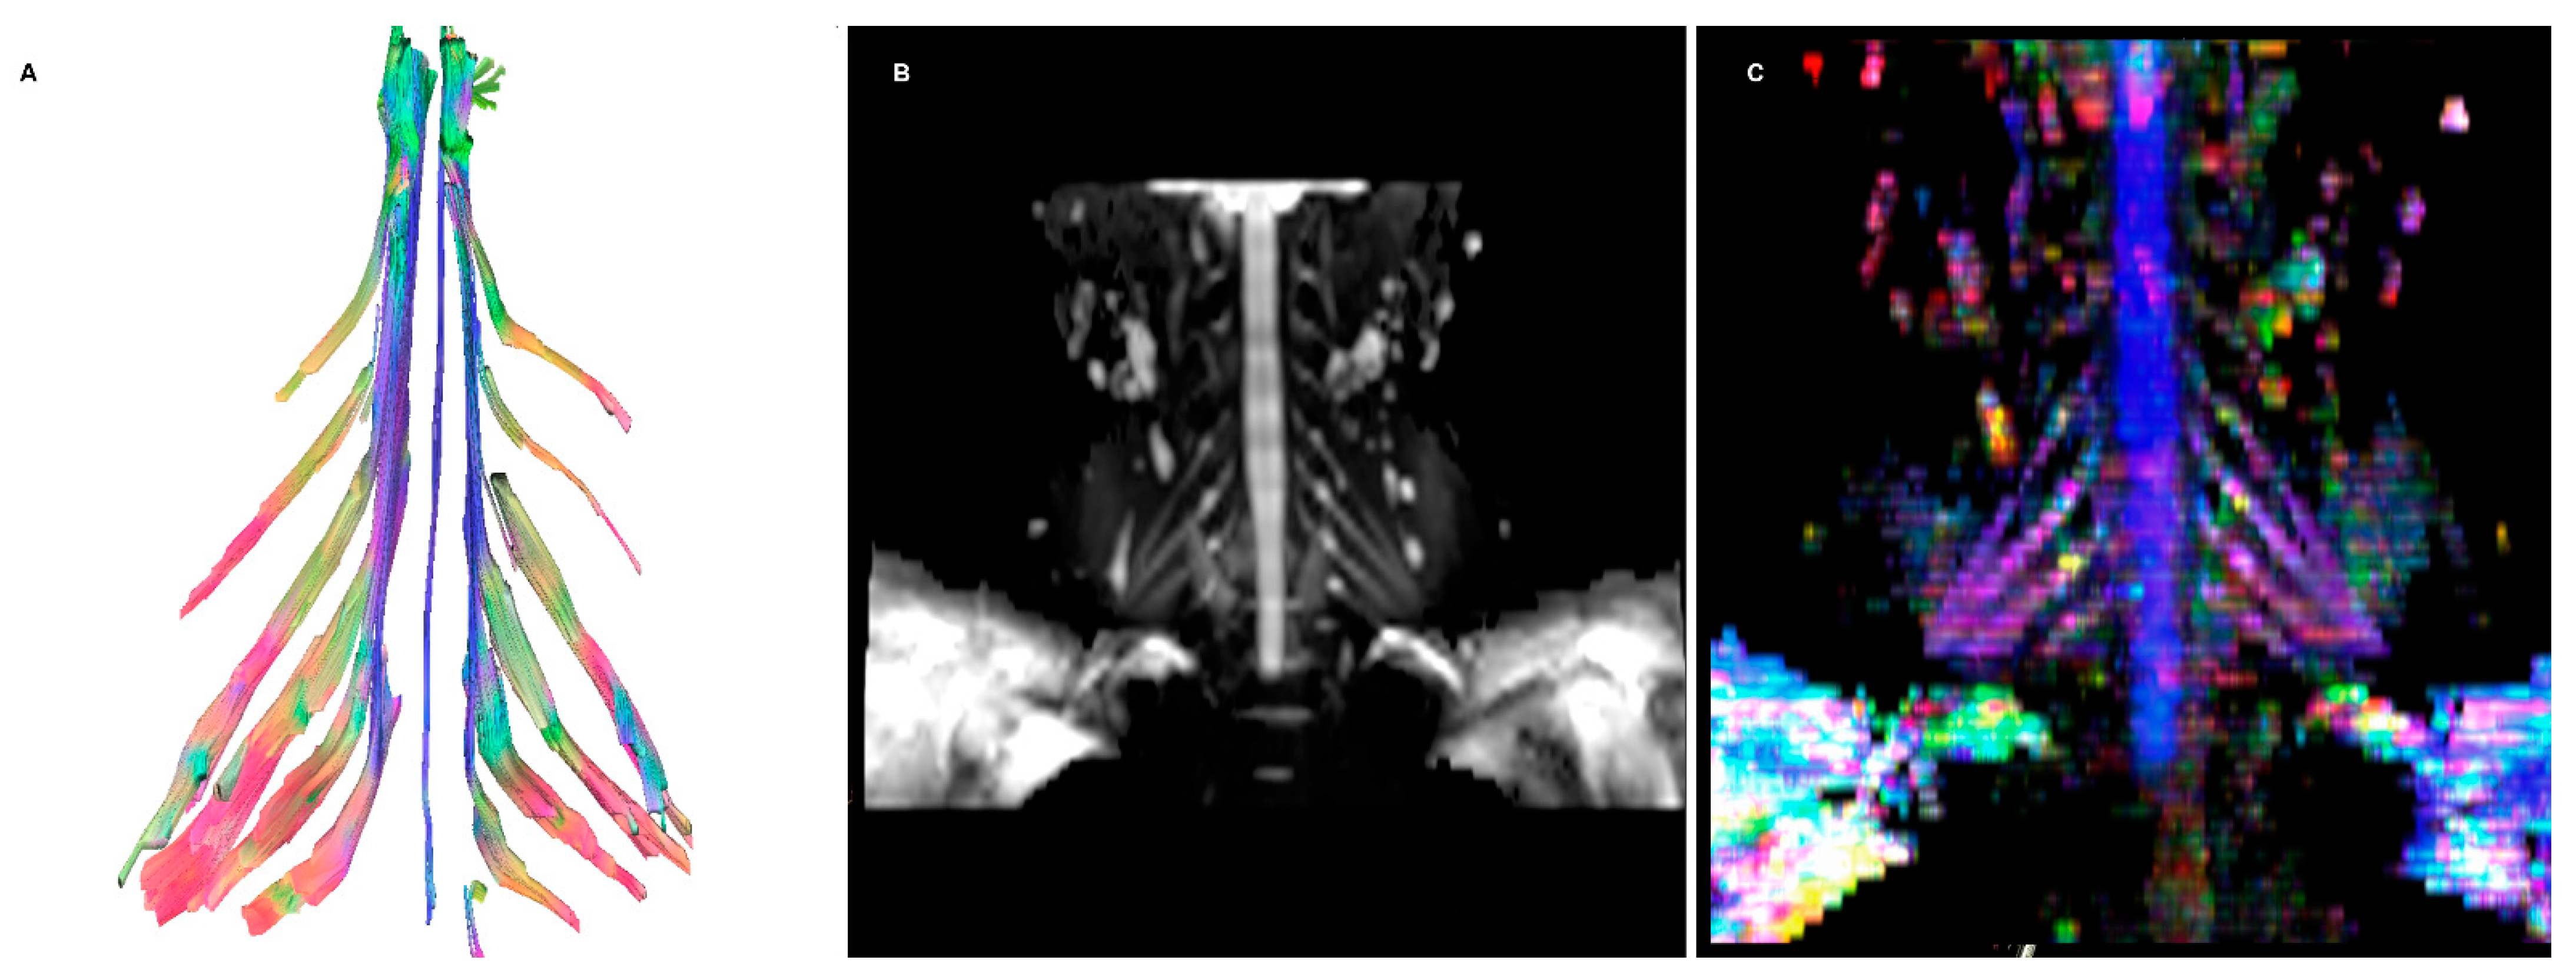

- DTI: Pioneered on the peripheral nervous system in the last decade, the DTI sequences provide the data to perform the nerve fiber tractography, clearly depicting the anatomy of the nerves and allowing to calculate novel in vivo biomarkers, such as fractional and more recently quantitative anisotropy [9,10]. Quantitative anisotropy is less susceptible to edema surrounding the fibers, so a decrease in fractional anisotropy alone should be regarded as edema, while a reduction in quantitative anisotropy is necessary to confirm a structural change [11]. In recent years, vendors have provided radiologists with proprietary applications to perform in-line post-processing, even if advanced studies are possible only on third-party software. Distortions caused by field inhomogeneity can be addressed with post-processing correction available in most software, with the optional addition of an inversed-encoding b0 sequence (“blip-in-blip-out” method) [12]. Manufacturers are addressing this topic by developing coils with a dedicated geometry [3]. A detailed visualization of the nerve fibers is extremely helpful in surgical planning, giving more information when choosing between nerve graft or a nerve transfer [13]. In the last few years, the multishell technique has emerged, and it consists of acquiring at least two DTI sequences with different b-values, increasing the accuracy of the tractography and reducing the in-scanner motion artifacts [14]. The multishell technique is being tested on the central nervous system, and very sparse applications on peripheral nerves have been published [15,16]. In this paper, the authors present a first attempt of multishell acquisition of the brachial plexus performed on a healthy volunteer (Figure 4). Diffusion signal in vivo originates from water represented in different structures, not only neurons but free water and glial cells as well. Conventional DTI-based fiber tracking results in a hampered representation of the tracks when they run in proximity to other water molecules with such different orientation modules, thus not matching the prediction of the Stejskal–Tanner equation:S = signal; b = b-value; D = Diffusion constant.